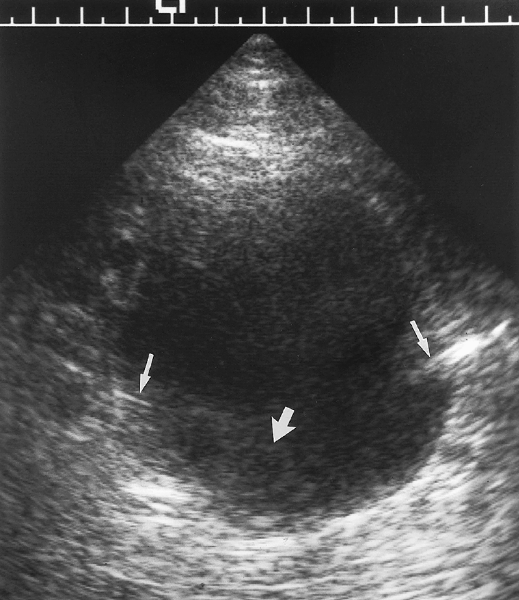

Gas-containing liver Abscesses: Assessment By Ultrasound (US ...

Gas-containing liver Abscesses: Assessment by Ultrasound (US) and Computed Tomography (CT) SA. Samad, FRCR MA. Zulfiqar, MMed (Radiology) whereas a ring-down artifact appears as a bright band consisting of a series of small, ... Fetch Full Source

Longitudinal ultrasound of the liver reveals multiple low density liver metastases foci with ring down artifact are seen within the left biliary tree con- • Michelle L. Rodgers, MD • Eric D. Sale, ... Get Content Here